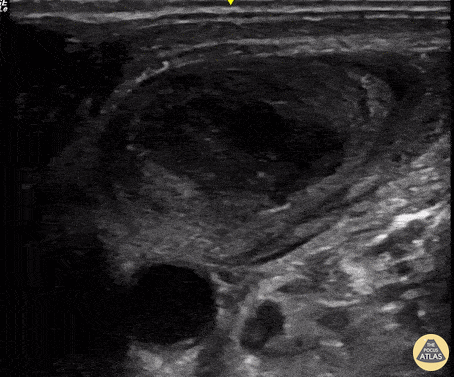

Vascular - Internal Jugular Thrombus

This POCUS was obtained using a linear probe and reveals a short axis view of an internal jugular vein containing a large thrombus. This highlights the importance of evaluating vascular structures with ultrasound prior to placing central lines. Renato Tambelli, Emergency Physician Hospital das Clínicas de Marília, Brazil @R_Tambelli // @JediPocus